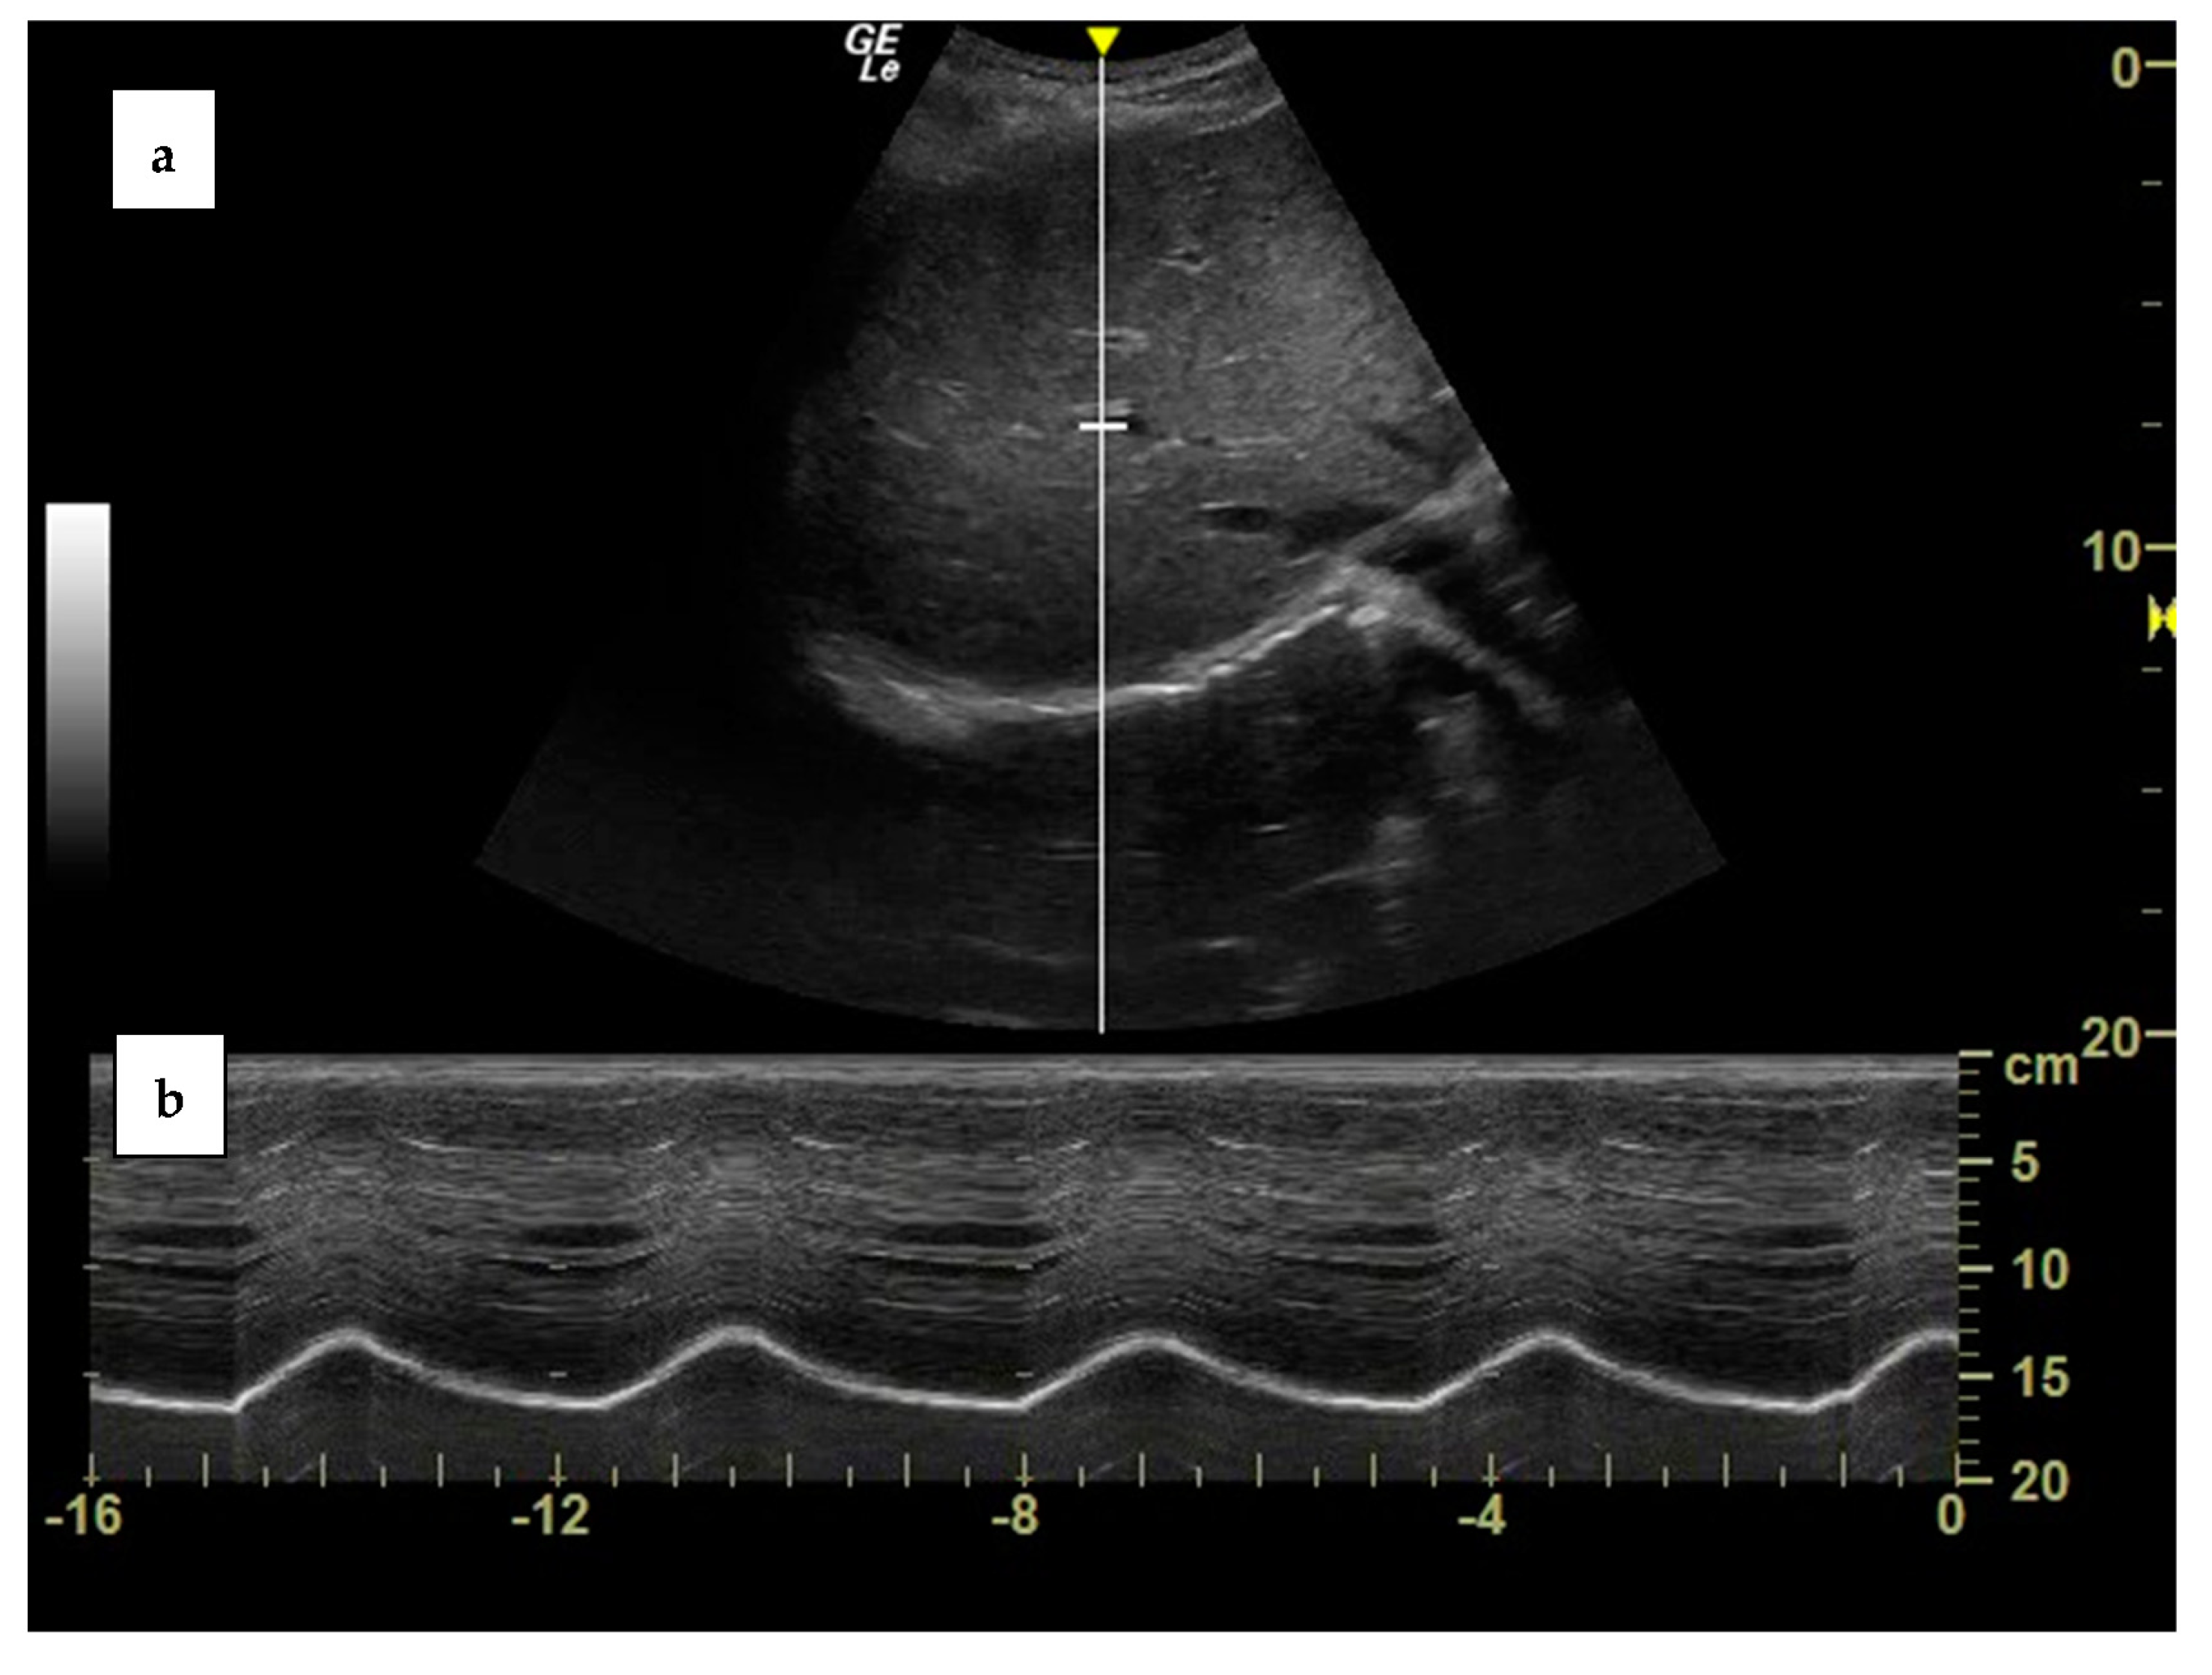

2. Diaphragm Function Assessment

3.1. Clinical Case One

3.2. Clinical Case Two

3.3. Case Discussion